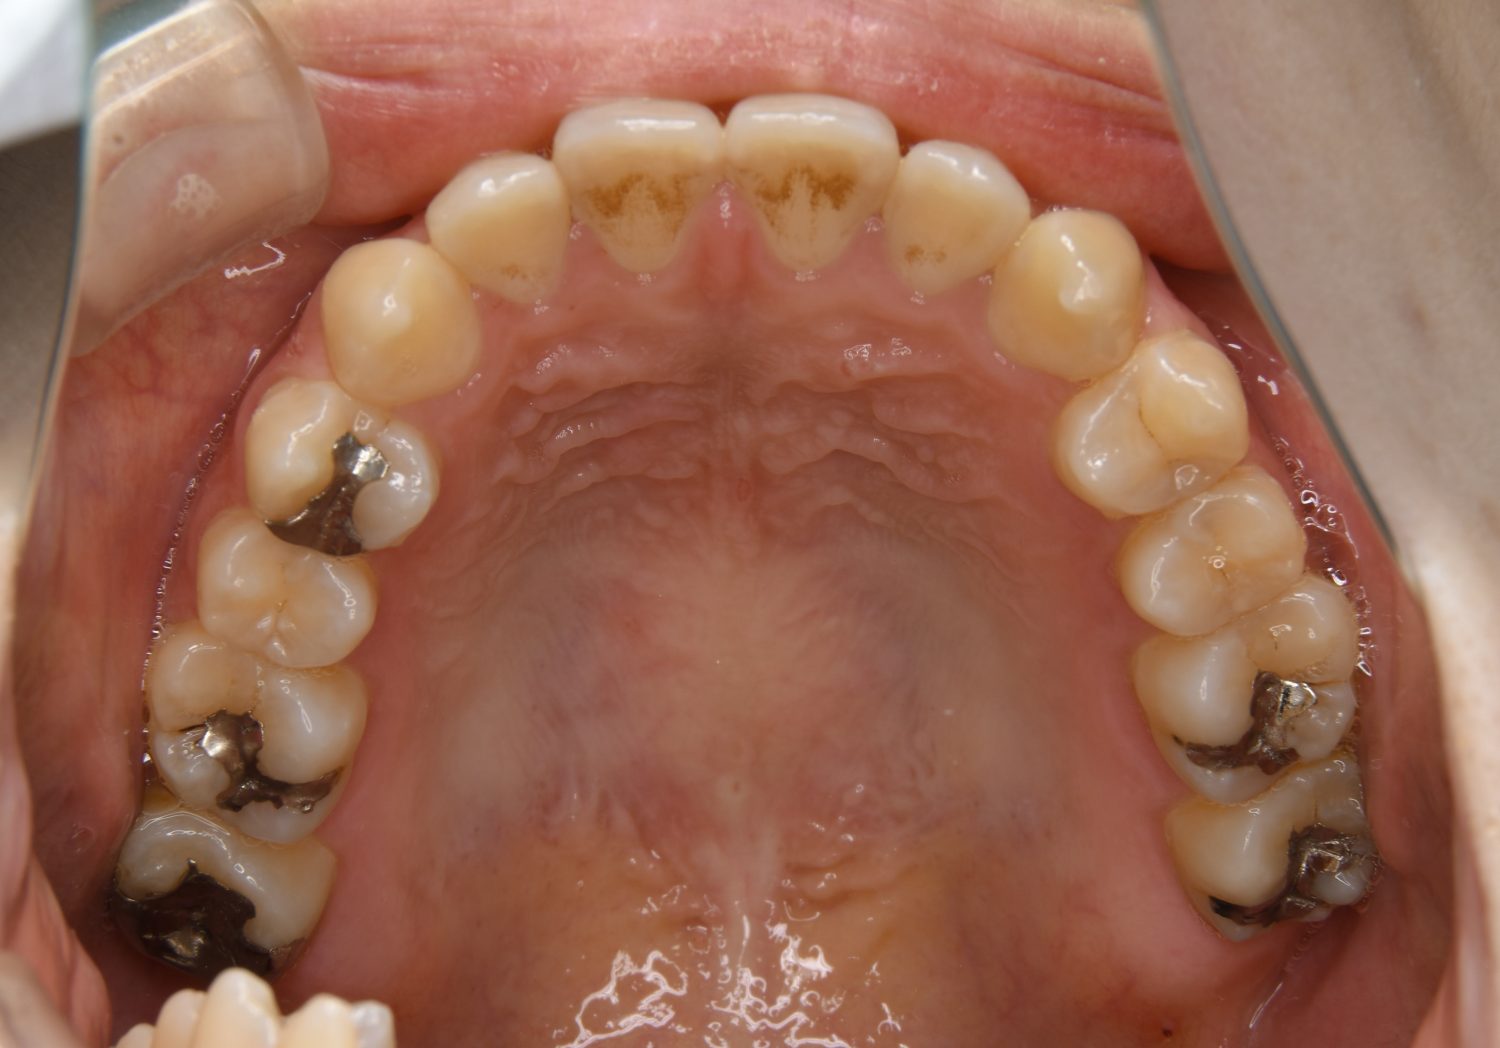

前歯部開咬の症例紹介①

Before

主訴

前歯が開いているのが気になる。

治療内容

上リンガルブラケット(舌側装置)、下ラビアルブラケット(唇側装置)に矯正用アンカースクリューを併用し非抜歯で治療を行いました。

上下の前歯が開いており前歯では全く噛めていない状態でした。臼歯の圧下を行うことで前歯でも咬合できるようになり機能面のみでなく審美面も著しく改善しました。